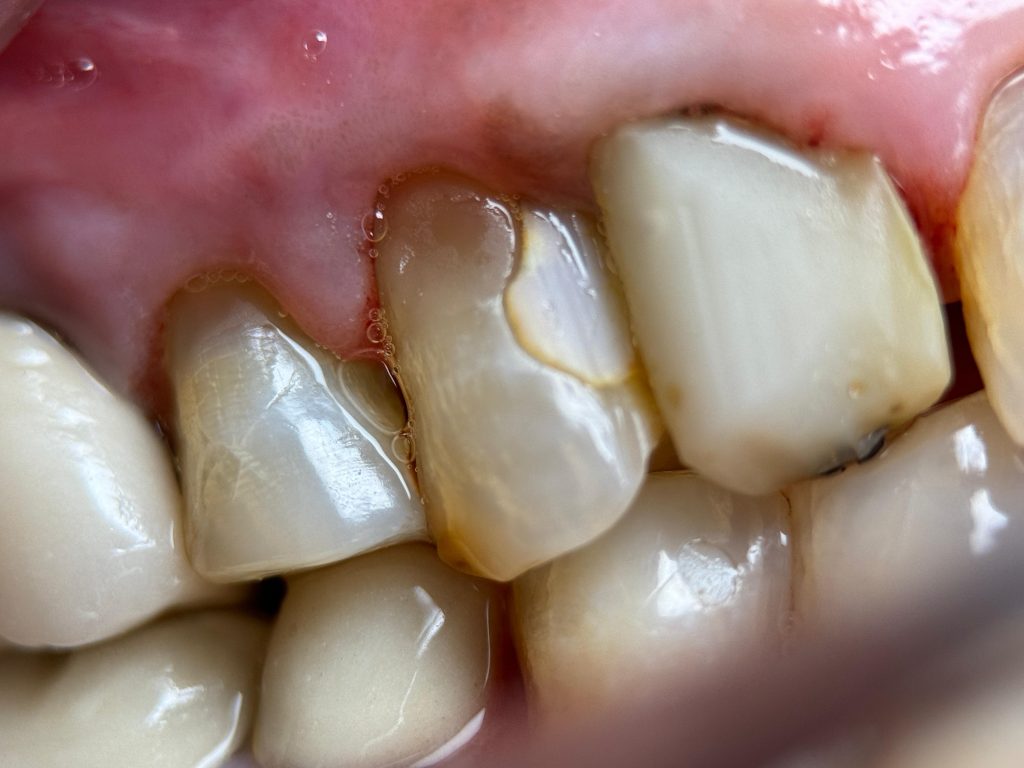

DEEP MARGIN ELEVATION (DME)

Subgingival distal margins were identified in UL6 and UL7. To avoid crown lengthening surgery and preserve periodontal architecture, Deep Margin Elevation (DME) was performed:

- Rubber dam inversion achieved for moisture control

- Sectional matrix band adapted

- Adhesive protocol followed

- SDR bulk flowable composite layered to elevate the margin supragingivally

- This allowed controlled impression, better crown fit, and long-term periodontal compatibility

FIVE-YEAR FOLLOW-UP

At 5 years:

- Tooth structure remained intact

- Prosthetic margins were stable

- Periapical radiographic healing was evident

- Patient remained asymptomatic

- Excellent gingival response observed

- No secondary caries or debonding

- Occlusion stable and functional

✅ Long-term quadrant stability achieved